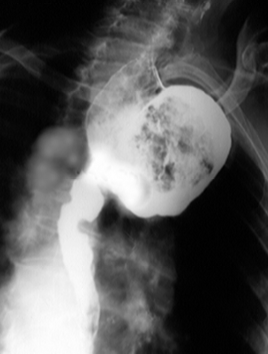

Hernie hiatală

Hernie hiatală prin alunecare

Hernie hiatală prin rostogolire